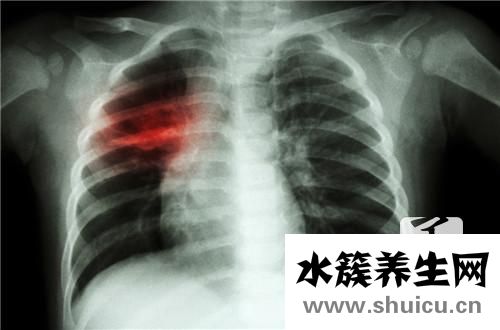

左侧后背心脏疼痛是日常生活中常见的情况。比如,发力不佳通常会导致背部韧带劳损,总是会出现这样的疼痛症状。如果持续有钝痛或跳痛,应引起警惕,可能是某些心脏病引起的,应认真做。

并且肺脏、心脏层面等病症,也是造成左后背疼痛的元凶。当背部疼痛主要表现比较轻度时,病人经常会忽略它的存有。可是,病症发展趋势到情况严重的水平,就需要认真完成,如腰椎的创伤骨折、结核病、肿瘤等。

左后背疼痛在病人出現左背部或右后背疼痛后,一般医师会建议病人做一个简易的查验,看一下肺脏是不是有感染,胸膜增厚是不是有炎症,或者有没有肺结核、心肌缺血等病症,此外,肋巴骨间神经炎、肋软骨炎等,乃至包含胃溃疡、十二直肠溃疡等病症,也会造成背部疼痛的。